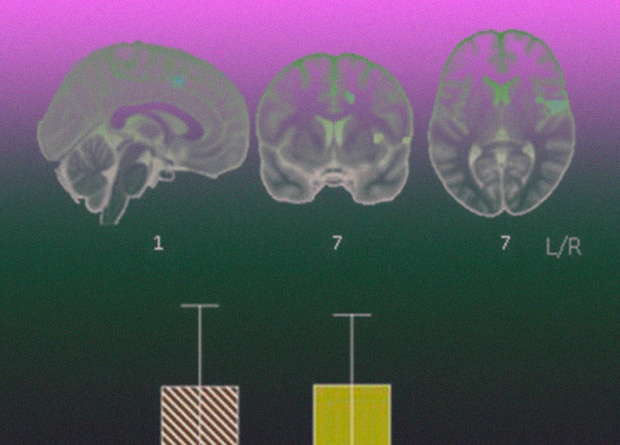

Британские исследователи выделили функциональные связи головного мозга, которые участвуют в формировании наркозависимости и устойчивости к ней при наличии факторов риска. Для этого они провели исследование с участием зависимых от стимуляторов добровольцев, их братьев и сестер без наркотической зависимости, а также людей, которые потребляли наркотики, но зависимость у которых не развилась. Риск развития наркозависимости определялся ослабленными связями между участками полосатого тела, входящего в систему вознаграждения, и префронтальными отделами, а при устойчивости к зависимости связи между ними (а также с моторными отделами) были намного прочнее. Судя по всему, при наличии факторов риска развития наркозависимости устойчивости к ней способствуют компенсирующие механизмы когнитивного контроля, пишут ученые в Proceedings of the National Academy of Sciences.